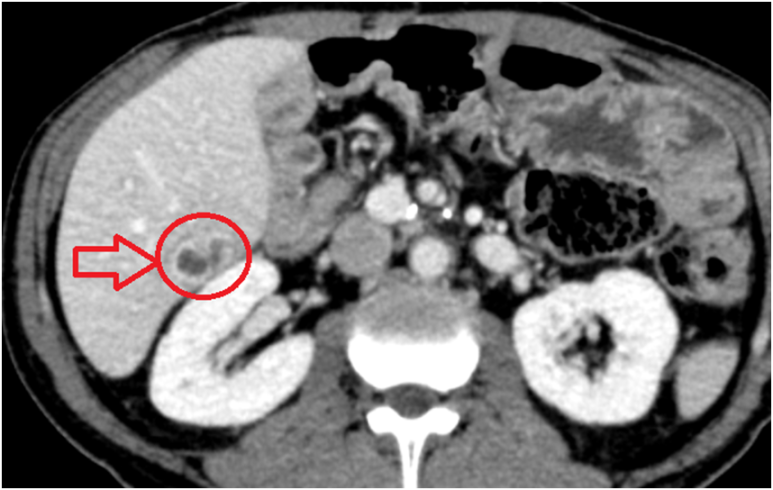

혈액검사 결과 간 기능·염증수치 상승 → CT에서 췌장쪽에서는 병변이 발견되지 않았고, 간 S6 농양 확인. 입원하여 항생제 치료가 필요하므로 원래 수술했던 병원으로 전원.

• CT: 간 S6 농양 CT: 간 S6 농양